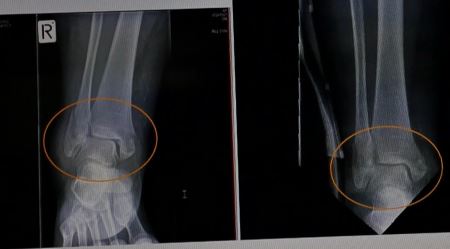

救护人员快速的把我抬到救护车上拉到急救中心,拍了很多X光照片。医生在X光片子上看到右腿有五处粉碎性骨折:右侧的踝骨和膝盖链接的腓骨完全断了,穿着裤子就可以明显看到骨折处的骨头向外支出;膝盖骨、右腿的左踝骨、右踝骨、右脚后跟,全部是粉碎性骨折。因为右腿肿的厉害,裤子已经绷的很紧,根本脱不下来,医生就用剪刀把裤子一块一块的剪掉。当时右腿一动也不能动。

图2:王久春女士2015年11月7日的踝关节X光片(左)与同年12月4日的X光片(右),对比可以看出,车祸3周后骨折处已有愈合趋势。

我是十一月十一日从医院回到家的。在十二月四日复查时,其它几个部位都在向好的方向发展,只有膝关节没有明显变化。医生说:“膝关节不可能恢复了,我也无法治疗,将来你不会正常走路。”当听到医生这话时,我脑中立即反映出:“你无法治,我师父能治!”对师父的那种坚信没有丝毫的含糊,没有丝毫怀疑。

十二月二十三日的复查显示:与十一月七日拍的片子相比较,能看到膝关节有明显的伤后愈合迹象;断骨端对位线良好;甚至那些骨头的碎片好像都是活的一样也在向自己原来的位置移动。